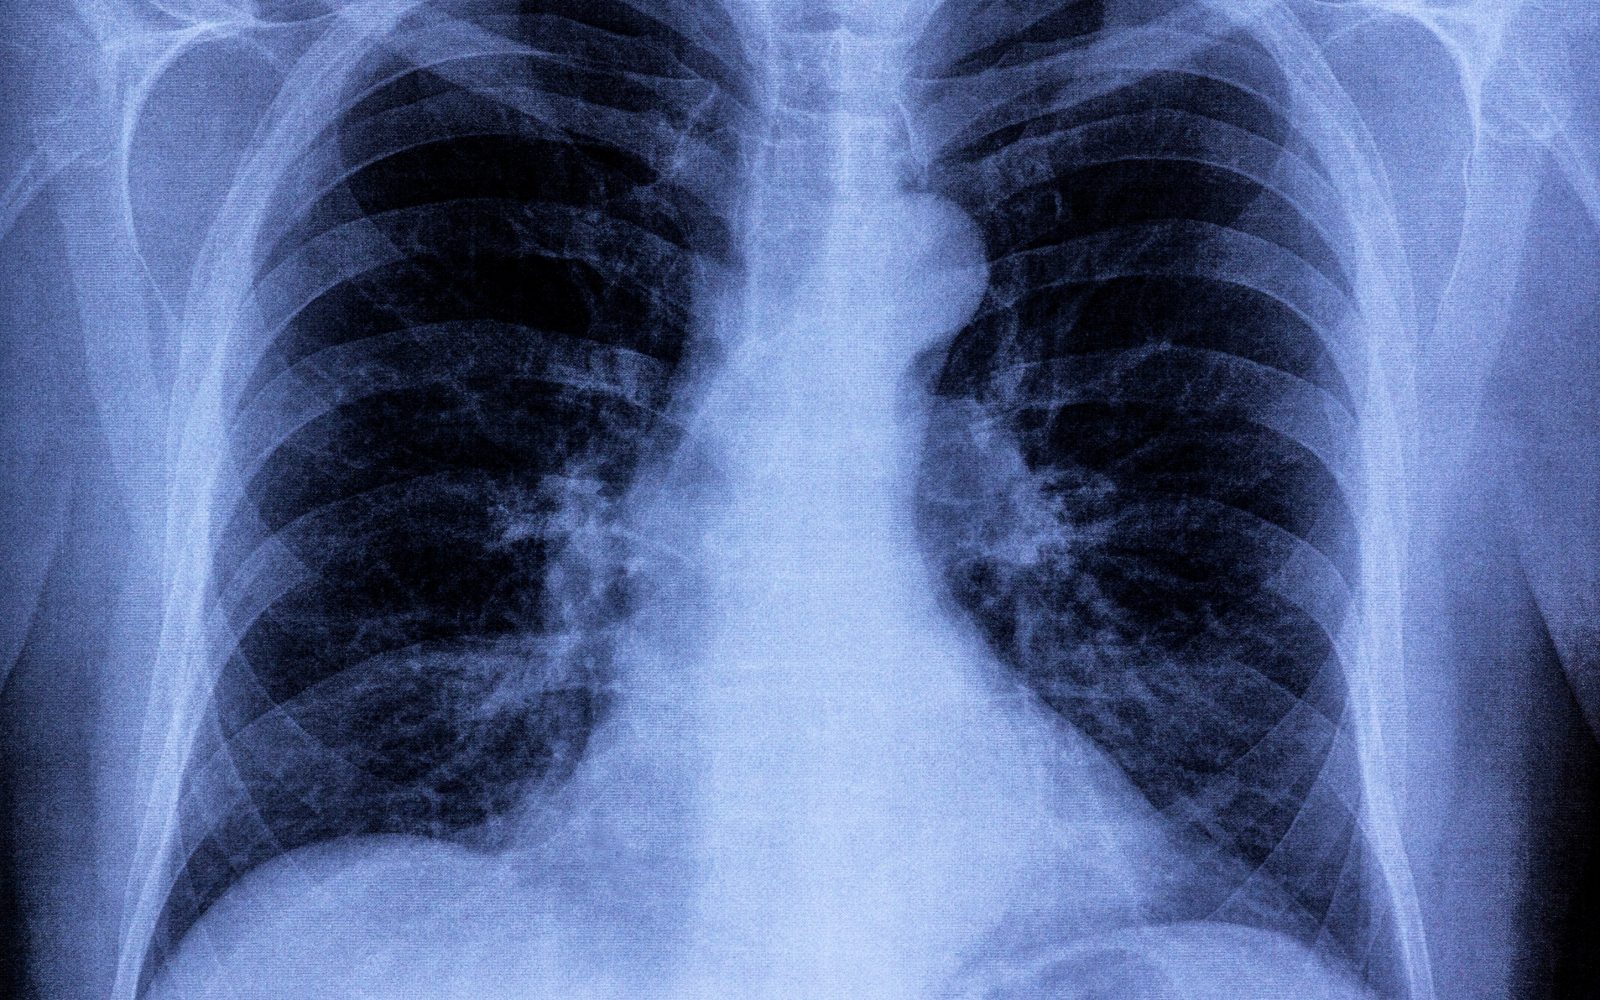

Nove raziskave so pokazale, da lahko celo blag primer covida poveča tveganje za srčno-žilne težave, vsaj eno leto po diagnozi. Raziskovalci so ugotovili, da so bile stopnje srčnega popuščanja in možganske kapi bistveno višje pri ljudeh, ki so preboleli covid, kot pri ljudeh, ki ga niso imeli. Tveganje je bilo povišano tudi pri mlajših od 65 let, ki niso imeli nobenih drugih dejavnikov tveganja, kot sta debelost in sladkorna bolezen.

Ljudje, ki so preboleli covid, so v letu po okužbi kazali znatno povečanje srčno-žilnih težav. Na primer, pri njih je bila za 52 odstotkov večja možnost za možgansko kap, kot pri kontrolni skupini.

Od 1000 anketiranih ljudi so bili približno štirje več v skupini s covidom kot v kontrolni skupini, ki je utrpela možgansko kap. Tveganje za srčno popuščanje se je povečalo za 72 odstotkov, oziroma za približno 12 oseb več v skupini ljudi s covidom na 1000 oseb. Hospitalizacija je povečala verjetnost prihodnjih srčno-žilnih zapletov, vendar so bili tudi ljudje, ki so se izognili hospitalizaciji, izpostavljeni večjemu tveganju za druge težave.